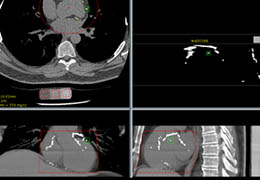

View X-Ray CT & MRI Scans Fast and Easily

Designed for surgeons, Pro Surgical 3D makes it easy to view patient scans quickly. Pro Surgical 3D facilitates the optimal 3D treatment and assessment workflows based on X-ray CT and MRI scans – and best of all, it’s FREE!

Traditional multi-planar slicing

High-quality and fast 3D reconstruction and 3D rendering

Performs 3D reconstruction and volume rendering.

Multi-planar slicing.

Oblique slicing.

Side-by-side comparative assessment for pre- and post-operative scans.